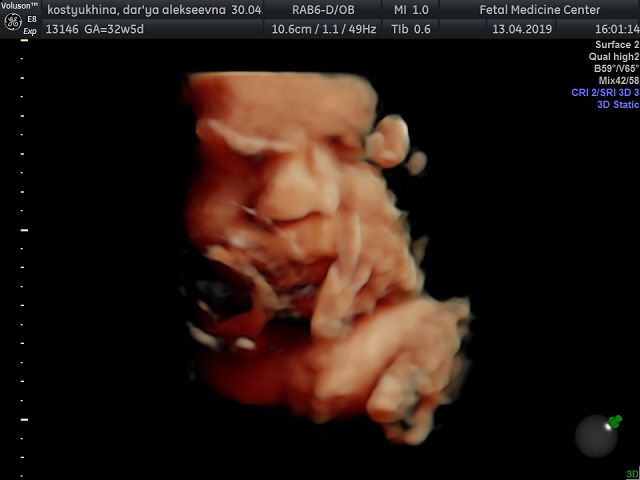

Вот и добралась до флешки))) Наш сыночек в цвете ? смотрю и не верю!!! Какое же чудо природы, да и техники фото через органы? еще 1,5 мес и состоится встреча всей жизни ? Вчера после скрининга зашли в кафе израильское, малыш ликует от этой пищи!!! С собой взяли паштет из тунца с кедровыми орешками и сушеной клюквой, села кушать и снова танцы ? блин даже от сладкого такого нет ? А что любят ваши малыши?)